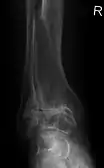

Diagnosis is made with reasonable certainty based on history and clinical examination.[51][52] X-rays may confirm the diagnosis. The typical changes seen on X-ray include: joint space narrowing, subchondral sclerosis (increased bone formation around the joint), subchondral cyst formation, and osteophytes.[53] Plain films may not correlate with the findings on physical examination or with the degree of pain.[54]

Primary osteoarthritis of the left knee. Note the osteophytes, narrowing of the joint space (arrow), and increased subchondral bone density (arrow).